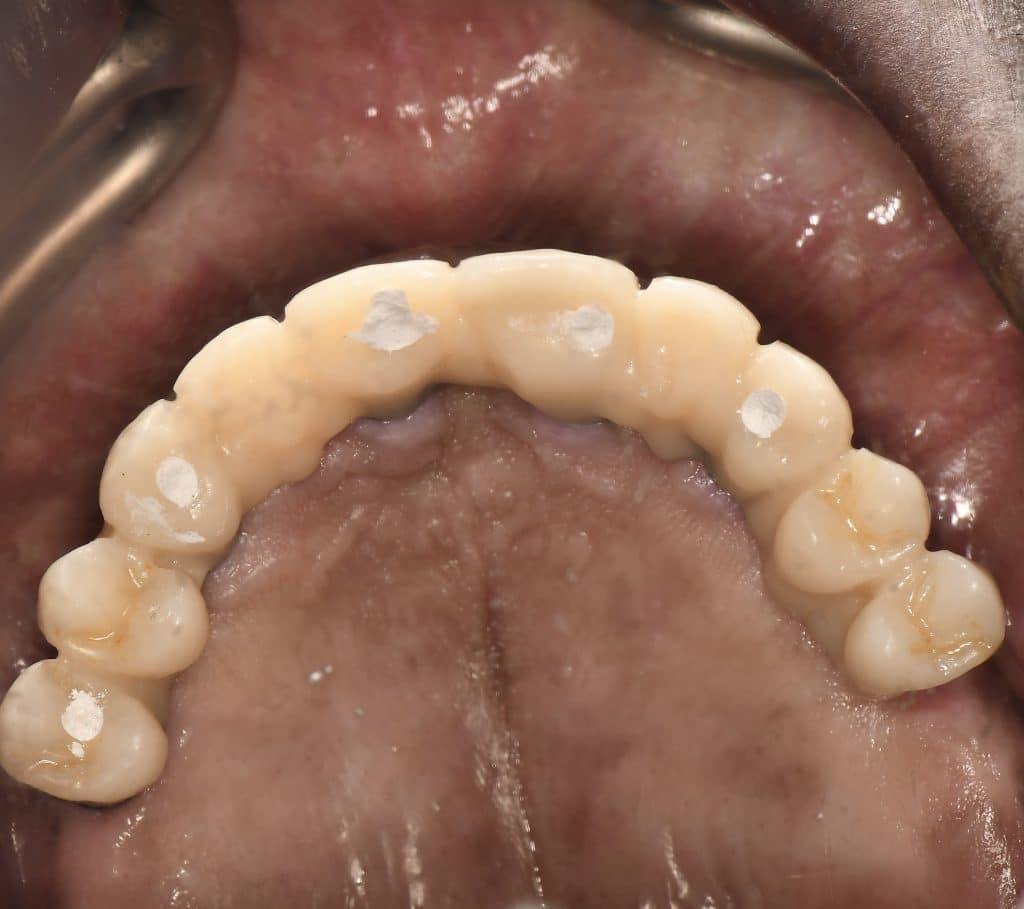

here a case where a full mouth réhabilitation was done by placing 6 implants

multiunit abutement were placed and a temporary bridge also was made for emergence profile shaping